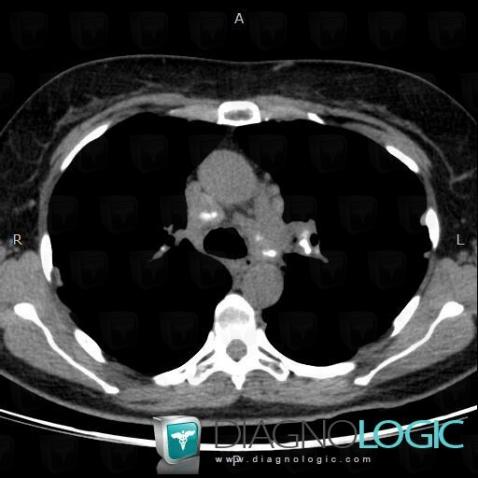

Les images ci-dessous illustrent ce dossier pour les diagnostics Sarcoïdose (lié à Fibrose pulmonaire), Sarcoïdose, pour les modalités (Scanner)

Voici les informations spécifiques à l'image clé ci dessus:

- Diagnostic Sarcoïdose, Localisation(s) Plèvre, comportant les gammes Epaississement pleural